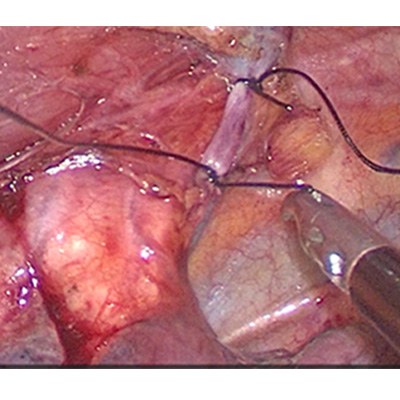

LAPAROSCOPIC WHIPPLES PROCEDURE

We have state of the art operating theatre with advanced surgical equipments. We have a Karl Storz Spies advanced HD laparoscopy operating system in addition to a 3 chip laparoscopy. We have installed advanced vessel sealing devices like Gen 11 harmonic scalpel, Ligasure from Valley Lab & Argon plasma coagulator. There is a recent addition of Cavitron Ultrasonic Aspirator (CUSA) system into our surgical armamentarium. We have the most recent powered Echelon endo-stapling devices. In addition to all these we have a constant supply of various types of advanced stapling devices for GI surgeries. Our endoscopy machines are having high definition with FICE Technology. Last but not the least we have semi flexible Ureteroscopy for managing common bile duct stones.

CAVITRON ULTRASONIC ASPIRATOR USED FOR LIVER RESECTION

LIVER RESECTION DONE USING CUSA